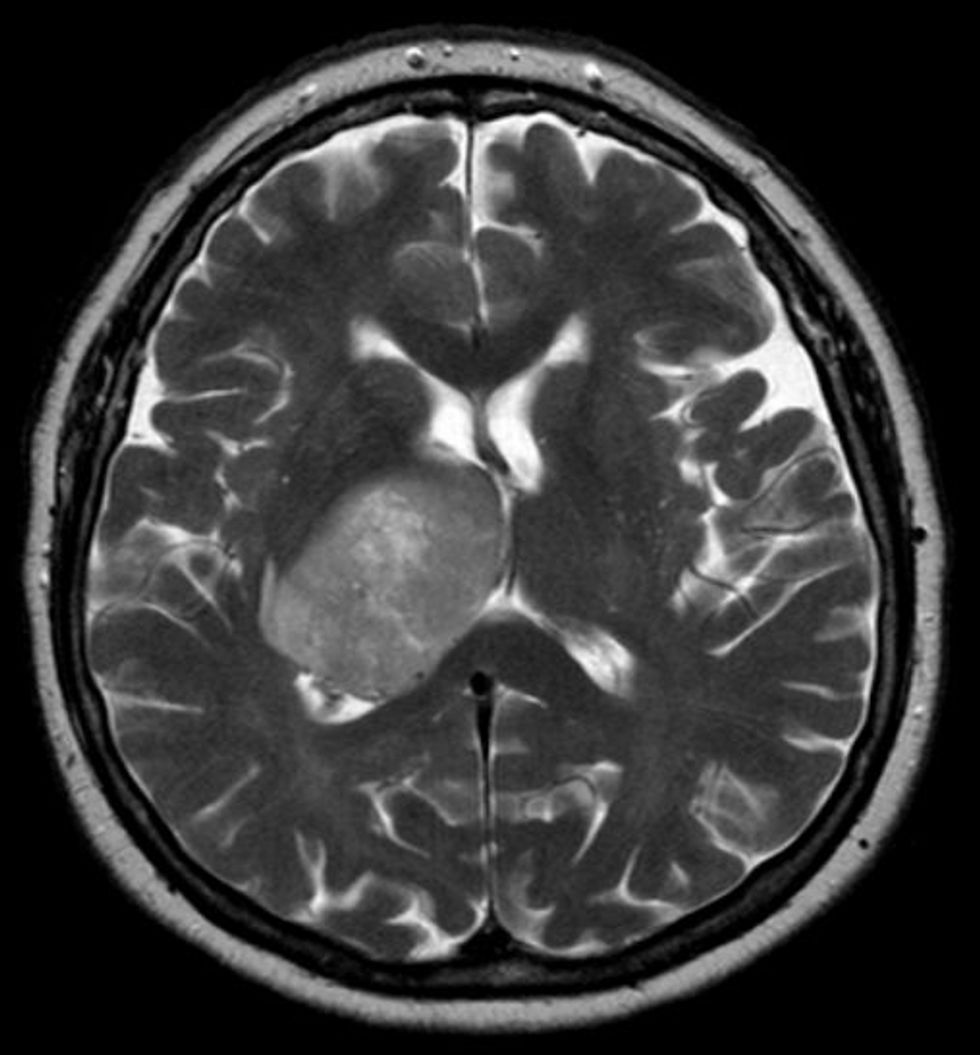

Phil Baumann, 47-year-old male, was diagnosed with an incurable form of brain cancer called Glioblastoma. He had a tangerine sized tumor in the right side of his brain that was removed through surgery, radiation and chemotherapy. Unfortunately, the tumor returned to his brain due to hidden cancer cells. He joined the clinical trial at MD Anderson Cancer Center at the University of Texas, where Dr. Juan Fueyo, M.D., and Dr. Candelaria Gomez-Manzano, M.D. were testing the Delta 24 cold virus.